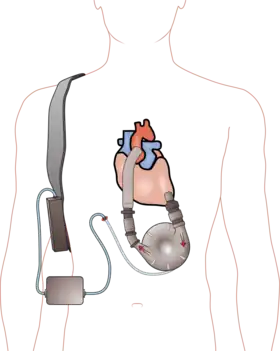

A left ventricular assist device (LVAD) pumping blood from the left ventricle to the aorta, connected to an externally worn control unit and battery pack. | |

A ventricular assist device (VAD) is an electromechanical device that provides support for cardiac circulation, which is used either to partially or to completely replace the function of a failing heart. VADs can be used in patients with acute (sudden onset) or chronic (long standing) heart failure, which can occur due to a variety of reasons (e.g. coronary artery disease, atrial fibrillation, valvular disease, and so forth).[1][2]